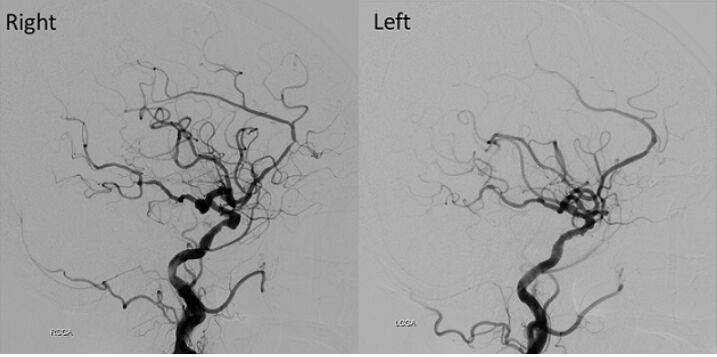

74.84歲女性,有高血壓病史,突然頭痛噁心而至急診求診。頭部電腦斷層檢查發現有廣泛蜘蛛網膜下腔出血 (subarachnoid hemorrhage, SAH)併腦室內出血;進一步做頭部血管攝影檢查,影像如附圖(右側及左側頸動脈造影),造成她SAH的原因最可能為下列何者? (A)右側內頸動脈(ICA)和後交通動脈(PCommA)交界腦動脈瘤 (B)左側內頸動脈(ICA)和後交通動脈(PCommA)交界腦動脈瘤 (C)右側前大腦動脈瘤 (D)左側前大腦動脈瘤